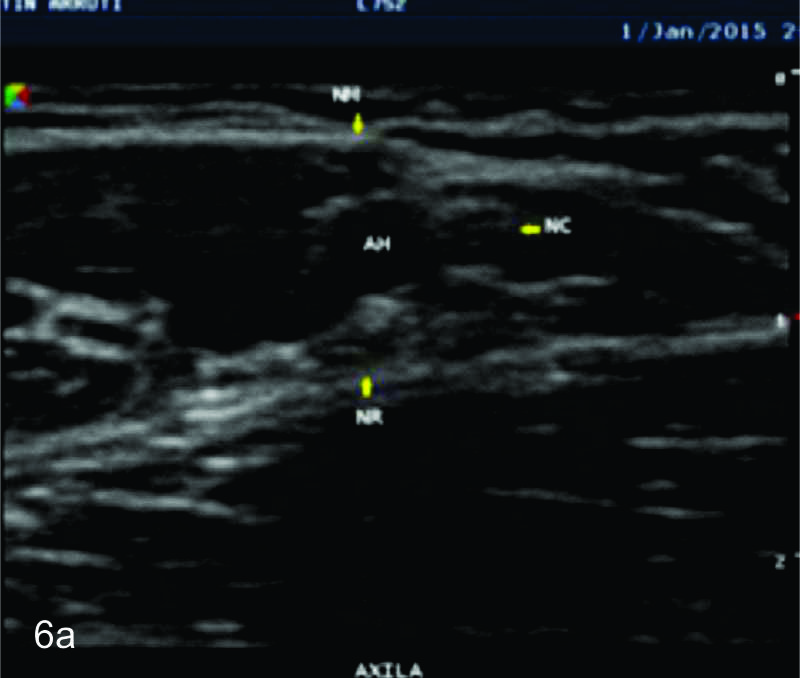

Figura 6

Nervio cubital

B- tercio medio del brazo,

C- tercio distal del brazo,

D- codo en canal epitrocleo-olecraneano,

E- codo- canal cubital,

F- tercio proximal antebrazo,

Figura 7

Serie de cortes axiales del nervio cubital desde su origen a nivel del hueco axilar hasta su terminación a nivel del canal de Guyon. Se identifica el mismo señalado por flechas amarillas y con las letras NC. AH-arteria humeral, PC- músculo prondador cuadrado, P- hueso pisciforme, Línea roja- ligamento anular del carpo, Línea amarilla- túnel de Guyon, Flecha azul- Arteria cubital-. A-tercio distal antebrazo, B- canal de Guyon.

Serie de cortes axiales del nervio mediano desde su origen a nivel del hueco axilar hasta el sector distal del antebrazo previo a su ingreso al túnel del carpo. Se identifica el mismo señalado por flechas amarillas y con la palabra mediano. AA-arteria axilar, VA- vena axilar, AH- arteria humeral, VH- vena humeral, VB- vena basilar, AC- ateria cubital, VC- vena cubital, BA- músculo braquial anterior, PR- músculo pronador cuadrado, FS- músculo flexos superficial, FP- músculo flexor profundo, PC- músculo pronador cuadrado. A- axila, se identifica el nervio superfical a la arteria axilar, B- tercio medio del brazo en canal bicipital medial, lateral a la arteria humeral, C- codo, medial al tendón distal del bíceps braquial y a la arteria humeral luego de cruzarla, superficial al músculo braquial anterior, D-antebrazo sector cefálico, entre las dos cabezas del pronador redondo, E- tercio medio del antebrazo, entre los músculos flexor superficial y profundo F- tercio distal antebrazo, superficial al pronador cuadrado.